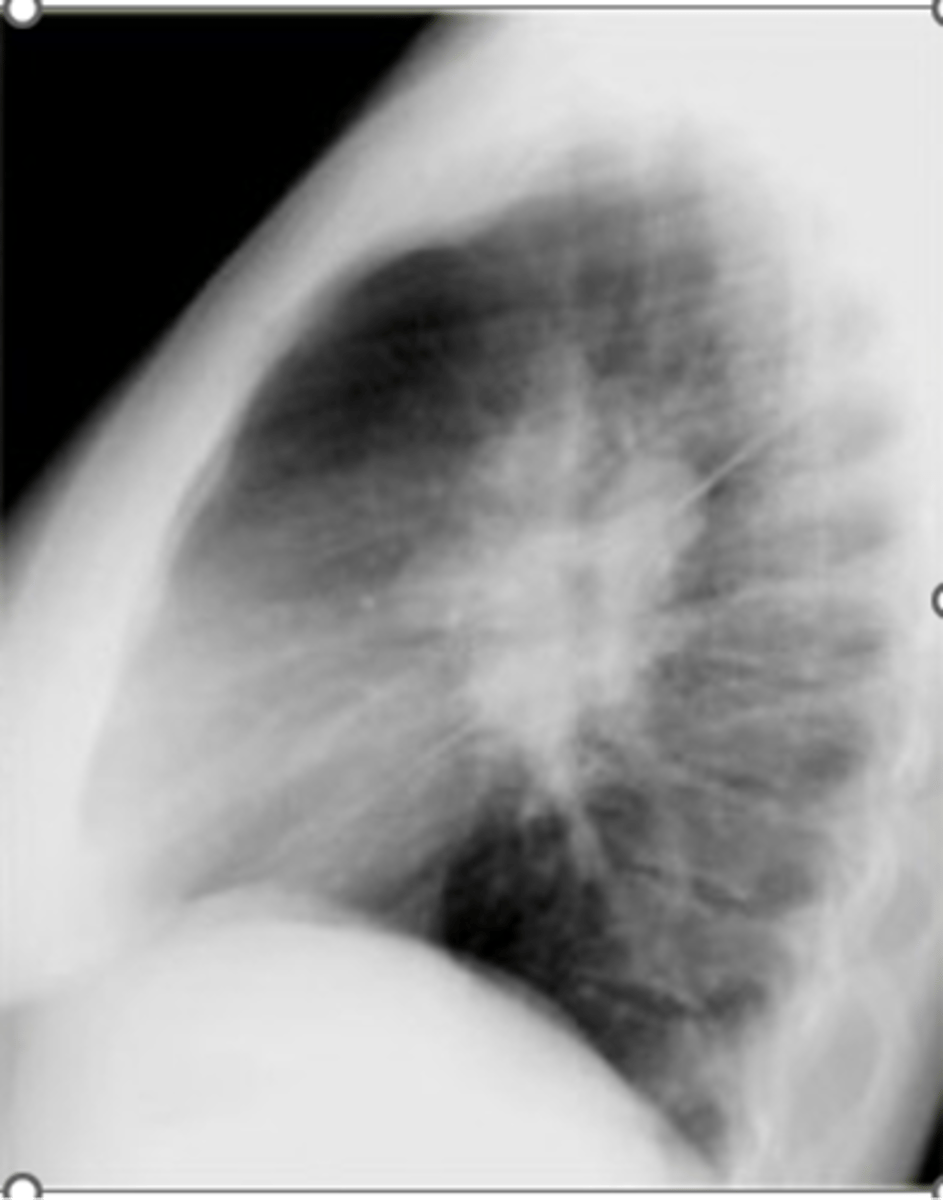

Asthma (hyperinflation with tram lines)

knowt flashcard image

asthma